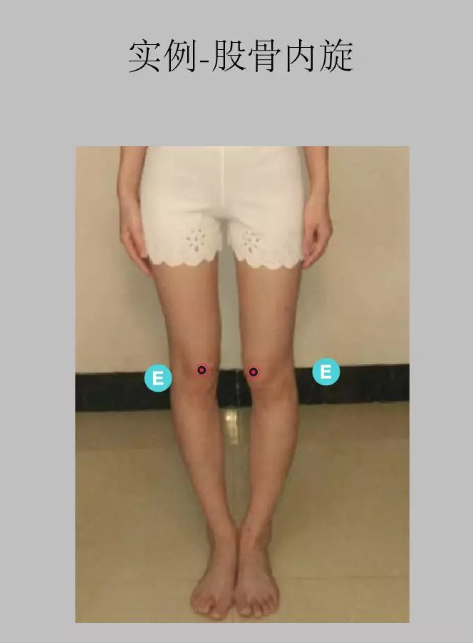

O 型腿:O 型腿有两种,一种是 膝关节 内翻,一种是股骨向内旋转。比较常见的是第二种,即由于 股骨内旋 导致的 O 型腿。正面观察时,两侧膝关节无法并拢,而且膝关节朝向内侧。如下图所示